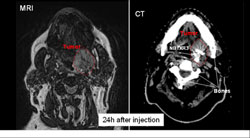

Ces résultats confirment également un bon profil de sécurité. Ainsi, aucun effet indésirable grave (SAE) lié au produit n’a été observé, et il apparaît que le produit reste dans la tumeur sans fuite dans les tissus sains environnants.